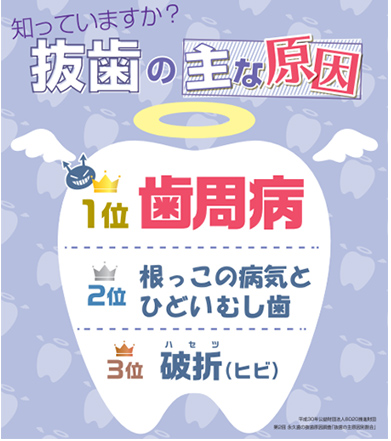

次の図を見てください。歯が抜かれてしまう3大原因を説明したものです。

1番多い原因は歯周病です。歯がグラグラになって抜けてしまう怖い病気です。

3番目は歯にヒビが入ったり、折れたりする事故です。

そして2番目が根っこの病気なのです。

医学が進んだ現代にあっても、歯周病と歯根の病気は不治の病なのです。歯周病になったり、歯の根っこが炎症を起こすとほぼ抜歯となります。大変残念なことですが、これは真実です。